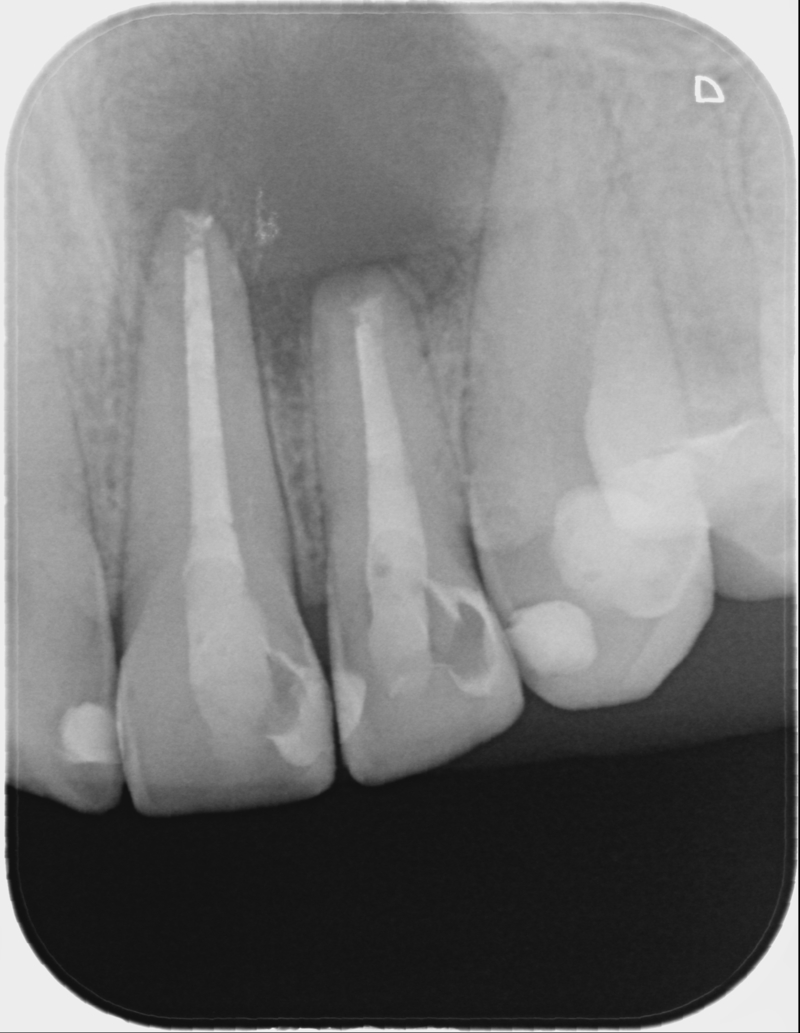

• Klinické vyšetření a rtg 2D a 3D diagnostika v reendodoncii, posuzování kvality předchozího

endodontického ošetření, množství a kvalita tvrdých zubních tkání, vertikální infrakce

a fraktury, resorpce, hluboký aproximální kaz.

• Definitivní plnění kořenových kanálků, hydraulická metoda, biokeramické sealery, vhodné

postendodontické ošetření.